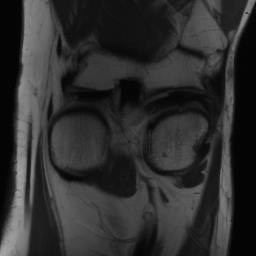

5.3 Out-of-Domain Generalisation

One way to test the generalization capability of the trained X-Diffusion is to test it on a completely different domain from an MRI dataset not seen during training. We report the single-slice results on NYU fastMRI [37, 82], a knee MRI dataset, using the X-Diffusion trained on the BRATS brain MRIs. The results are shown in Figure 9 and Table 2. It shows how successfully X-Diffusion is able to generate knee MRIs from a single image, despite not seeing knees at all in training. To qualitatively assess how realistic our generated 3D volumes were (produced from a single slice), we gave 20 generated examples alongside their real MRI counterparts to an expert orthopaedic surgeon. He was then asked to identify the real example from a given pair. The surgeon identified with certainty only 10 real knee MRIs out of 17, while could not decide on the remaining 3 of the 20 MRI pairs. This further validates the generated out-of-domain MRIs.